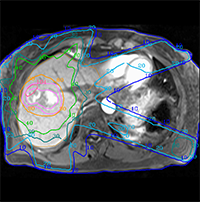

MRI Guidance for Radiation Oncology

Radiation therapy is benefiting from recent research aimed at integrating MRI into radiotherapy planning and guidance. Recent years have seen the rapid adoption of dedicated MRI systems as simulators that give better visualization of the tumor and surrounding healthy tissue. By bringing MRI directly into the treatment room, new systems offer the potential to guide high-precision radiotherapy by virtue of such improved imaging capability. A special symposium on Tuesday, July 22, features the latest research on bringing MRI into the process of radiotherapy planning, guidance and evaluation of treatment response.

Radiation therapy is benefiting from recent research aimed at integrating MRI into radiotherapy planning and guidance. Recent years have seen the rapid adoption of dedicated MRI systems as simulators that give better visualization of the tumor and surrounding healthy tissue. By bringing MRI directly into the treatment room, new systems offer the potential to guide high-precision radiotherapy by virtue of such improved imaging capability. A special symposium on Tuesday, July 22, features the latest research on bringing MRI into the process of radiotherapy planning, guidance and evaluation of treatment response.

Additional studies related to this topic »

| SU-C-17A | MR-Guided Radiation Therapy Seven oral presentations. Topics include: use of MRI for radiation treatment planning, registration of MRI and CT, and managing patient motion in MRI. |

| WE-G-17A | MRI in the Treatment Room Nine oral presentations. Topics include: integration of MR scanner and linear accelerator, tumor tracking, physics and engineering of MRI in the treatment room, and MRI guidance of brachytherapy. |